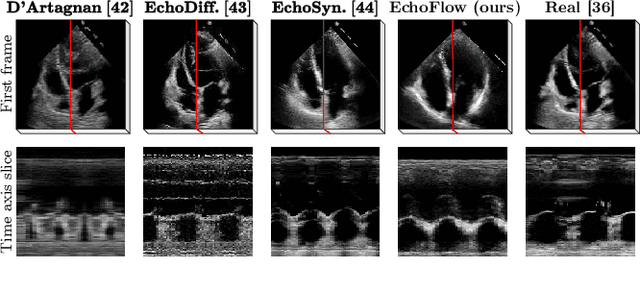

Abstract:Advances in deep learning have significantly enhanced medical image analysis, yet the availability of large-scale medical datasets remains constrained by patient privacy concerns. We present EchoFlow, a novel framework designed to generate high-quality, privacy-preserving synthetic echocardiogram images and videos. EchoFlow comprises four key components: an adversarial variational autoencoder for defining an efficient latent representation of cardiac ultrasound images, a latent image flow matching model for generating accurate latent echocardiogram images, a latent re-identification model to ensure privacy by filtering images anatomically, and a latent video flow matching model for animating latent images into realistic echocardiogram videos conditioned on ejection fraction. We rigorously evaluate our synthetic datasets on the clinically relevant task of ejection fraction regression and demonstrate, for the first time, that downstream models trained exclusively on EchoFlow-generated synthetic datasets achieve performance parity with models trained on real datasets. We release our models and synthetic datasets, enabling broader, privacy-compliant research in medical ultrasound imaging at https://huggingface.co/spaces/HReynaud/EchoFlow.